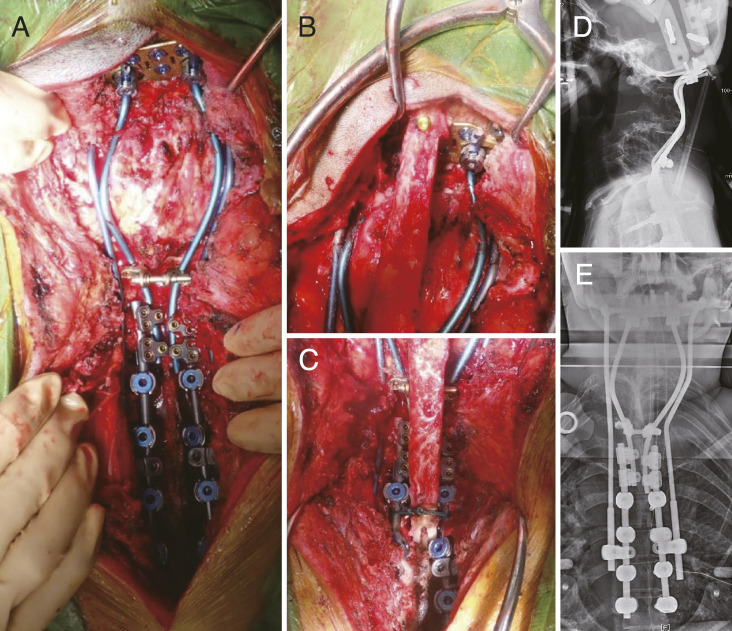

Treating Severe Cervical Deformity in Neurofibromatosis 1 with a Posterior Fibula Graft from Occiput to Thoracic Spine: A Case Report.

用枕骨到胸椎的后腓骨移植治疗神经纤维瘤病 1 的严重颈椎畸形:病例报告。